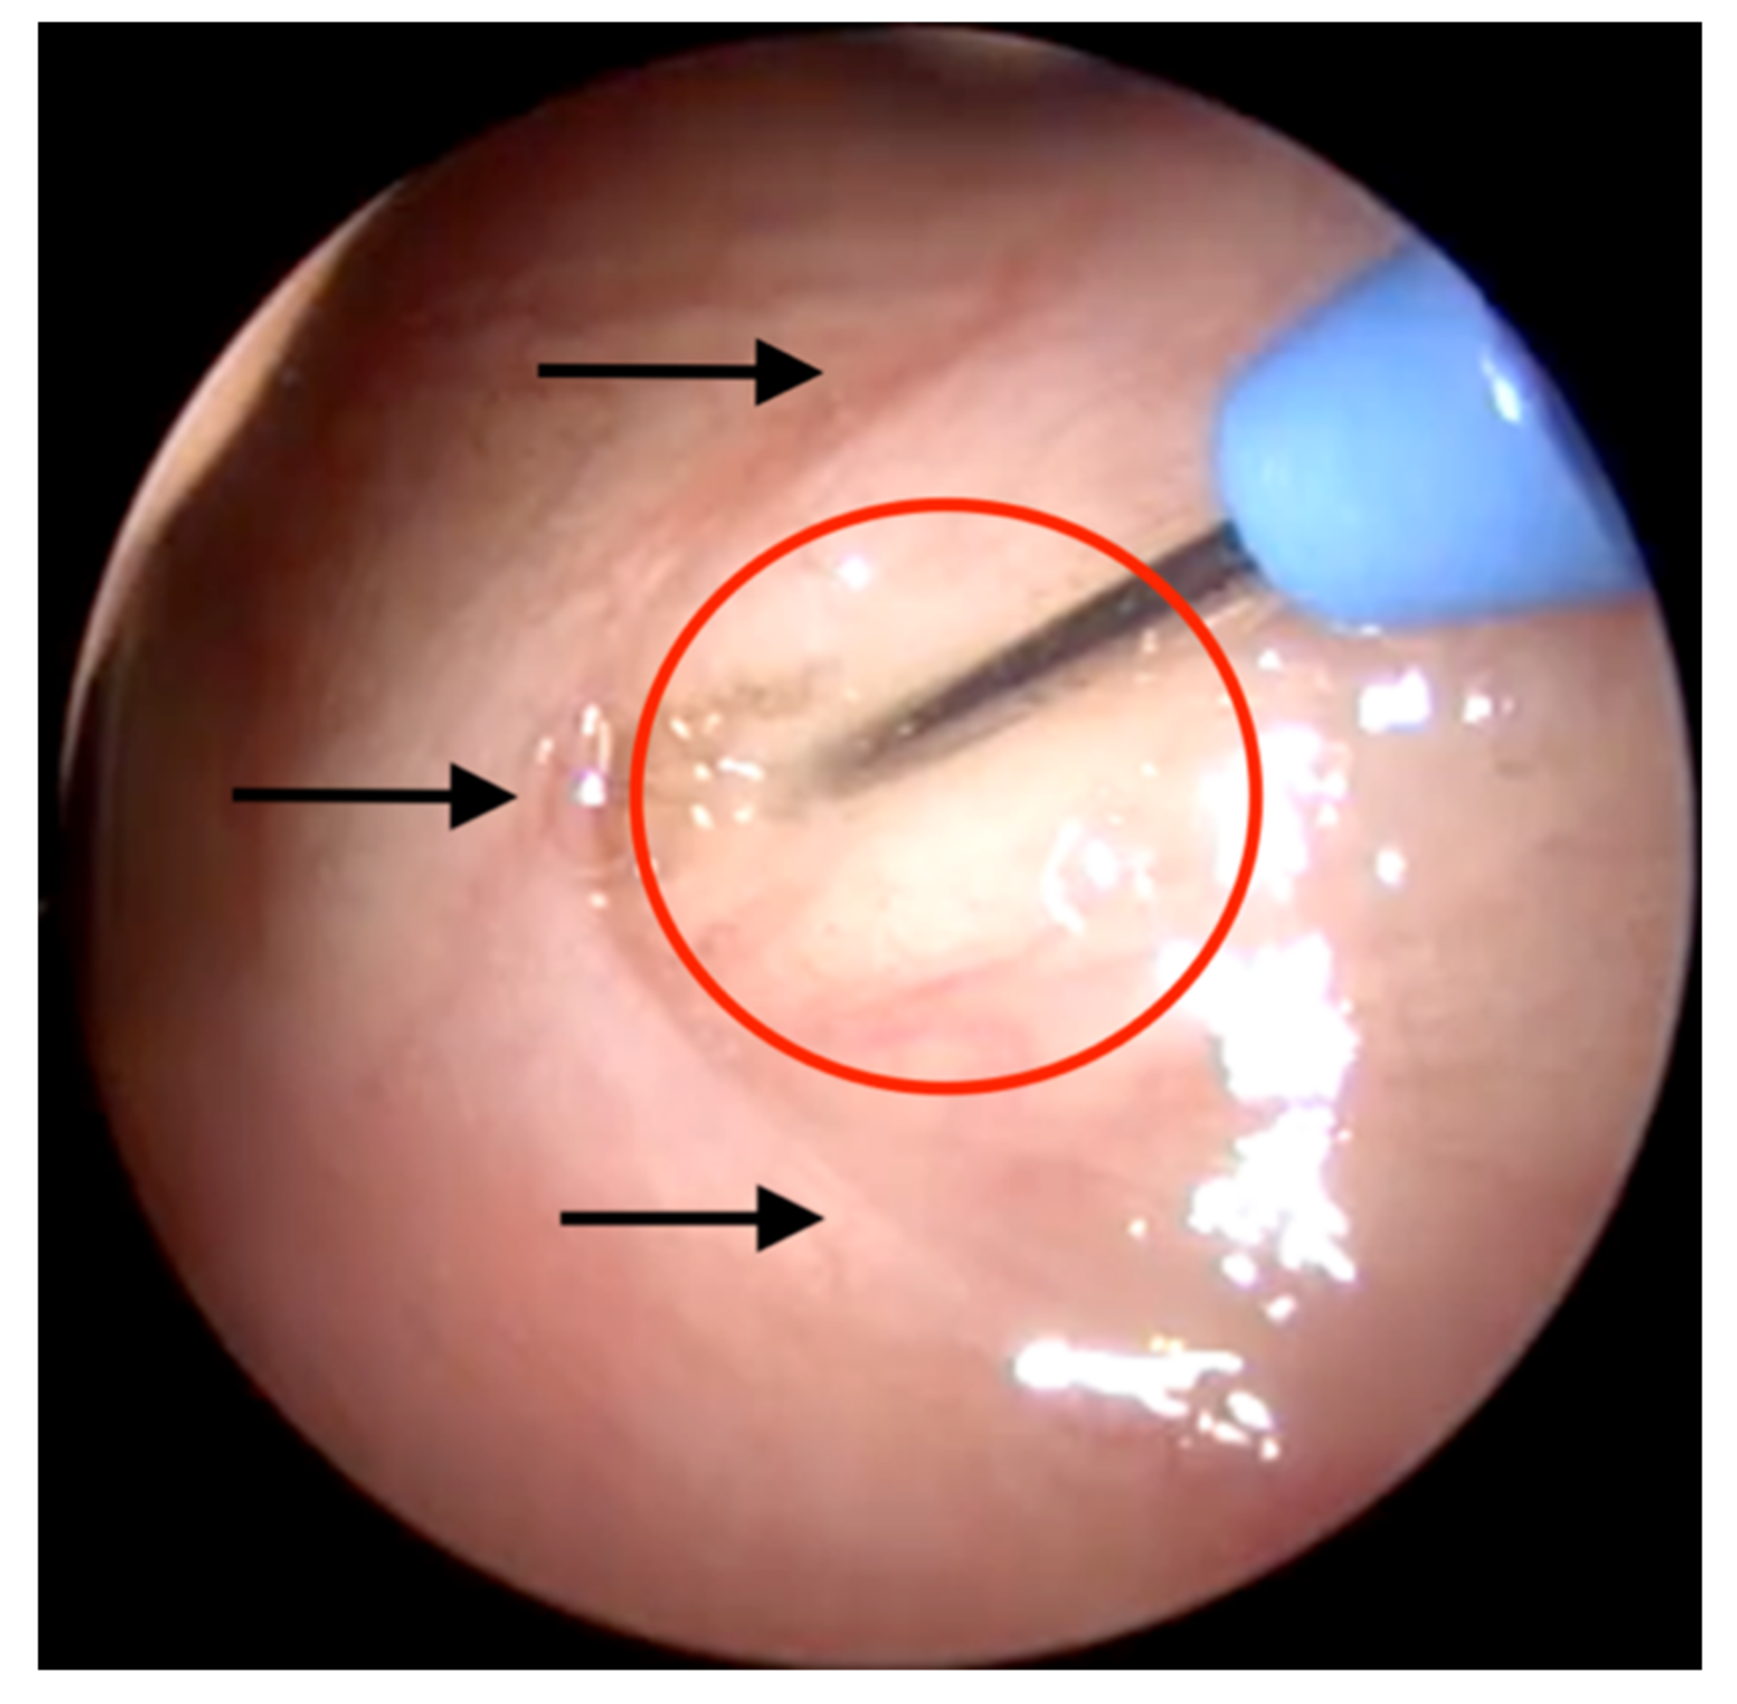

3.2.4. Imaging